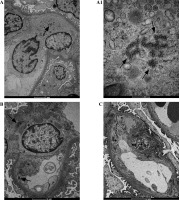

The evaluation of the biopsy samples in a light microscope revealed class III LN in five cases (50%), class II in three cases (30%), and class IV and class V in two individual cases (Table 1). Ultrastructural analysis of the biopsy material showed the presence of TRIs in seven patients (Table 3). These structures were most often found in endothelial cells of both the vascular bundle and the peritubular capillaries. They were occasionally observed in monocytes within capillaries and mesangial fields (Fig. 1). TRIs occurred within the irregularly widened cisterns of the endoplasmic reticulum. Some of them presented signs of pronounced swelling, which led to disruption of the surrounding membranes. In some inclusions, the tubular structures came into close contact with the membranes of the endoplasmic reticulum (Fig. 2). Both the size of the inclusions and the frequency of their occurrence varied among specimens (Fig. 3). The size of the TRIs varied in the range 300-1600 nm. Numerous TRIs (several inclusions in one glomerulus) were found in the biopsy of a patient with class V LN. All patients were tested for the most common viral infections connected with presence of TRIs (HIV, HBV, HCV, EBV, CMV) and all those disorders were excluded by performing simple blood tests. Only in one patient, after three years of treatment, was the re-biopsy performed. TRIs were still present in the specimen, but they were much less abundant (Fig. 4). In three cases with the highest presence of TRIs, the disease began before puberty (at 8-10 years of age), and in all these cases hematological disorders such as leukopenia, anemia, and thrombocytopenia preceded the LN diagnosis. Inclusions in a typical location, near subendothelial deposits, were observed in only one patient (Fig. 5). Biopsies of three patients with disease onset in adolescence (around 14 years of age) revealed no TRIs in the sampled material. In these patients, arthritis and nephrotic proteinuria dominated the clinical picture.

Fig. 4

The figure shows two biopsies of Patient 6. The first biopsy was performed in 2012: A) TRI structures (arrows) are present in a monocyte, B) endothelial cells and within mesangial area; A1) Enlargement of the photo (A) revealing details of the ultrastructure of TRI structures. The second biopsy (C) performed 3 years after initiation of treatment revealed absence of TRIs

In their work, Tranesh [25] suggested a relationship between the number of TRIs and the nature of histopathological changes in glomeruli, which are the basis for the LN classification. The author showed that the number of TRIs correlated with the ISN/RPS LN class: the increased number of TRIs correlated with class III, IV (proliferative forms) and V (membranous glomerulonephritis – MGN). In cases of MGN, the formation of TRIs was found in 100% of cases [24]. In our study, class V LN was diagnosed only in one patient. We found numerous clusters of TRIs in the ultrastructural image of this patient’s renal biopsy. In the re-biopsy performed after 3-year treatment resulting in remission, these inclusions were still present, but less abundant. In our study group, the proliferative forms of LN dominated, which is typical of jSLE. Due to the small size of the study group, it was impossible to correlate the amount of TRIs in the biopsy with the LN class.